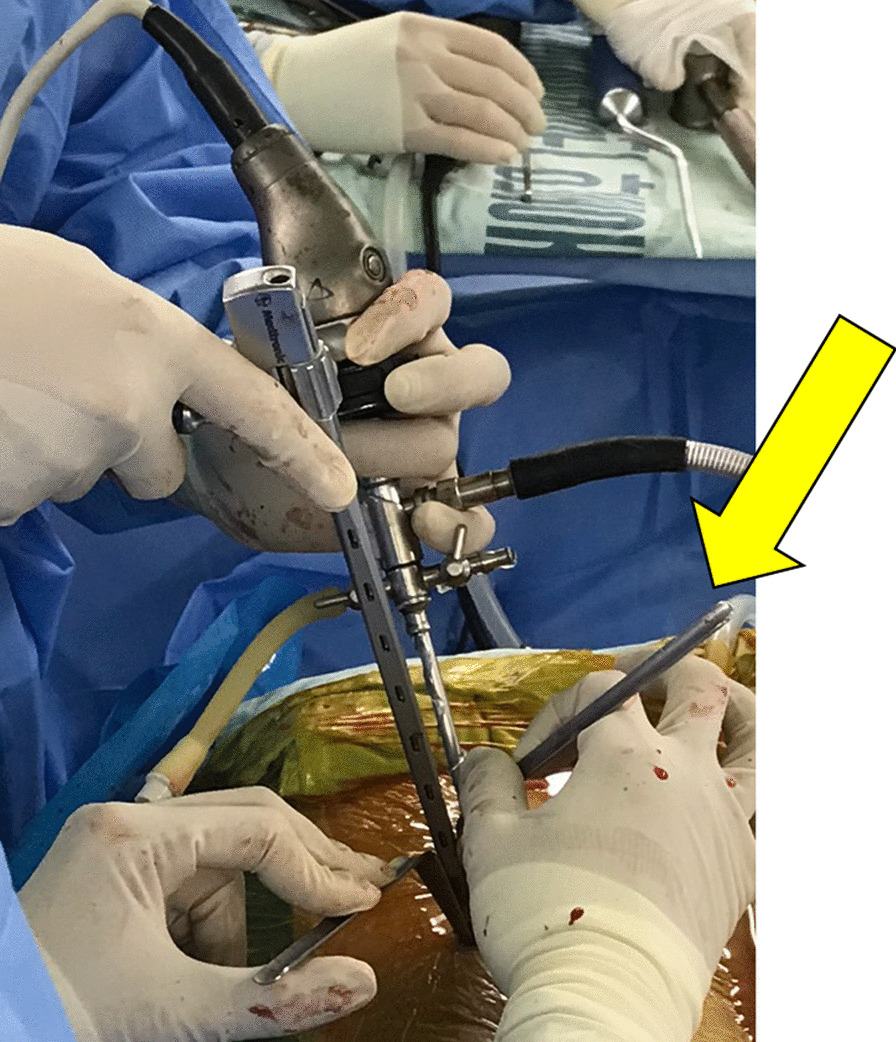

Notably, a special channel could be placed for intervertebral bone grafting and a specially designed retractor was used to fully expose the incision and protect the nerve root (Fig. 8). Thus, the cage could be implanted into the intervertebral space with the assistance of endoscopy and fluoroscopy, which is undoubtedly an advantage over uniportal endoscopy [27]. The internal fixation method is similar to that of minimally invasive TLIF (MIS-TLIF) and is done using a percutaneous pedicle screw system with fluoroscopy-guided screw placement. In BLIF, percutaneous screws can be placed using the original channel.

Fig. 8.

A specially designed retractor (yellow arrow) is used to fully expose the incision and protect the nerve root